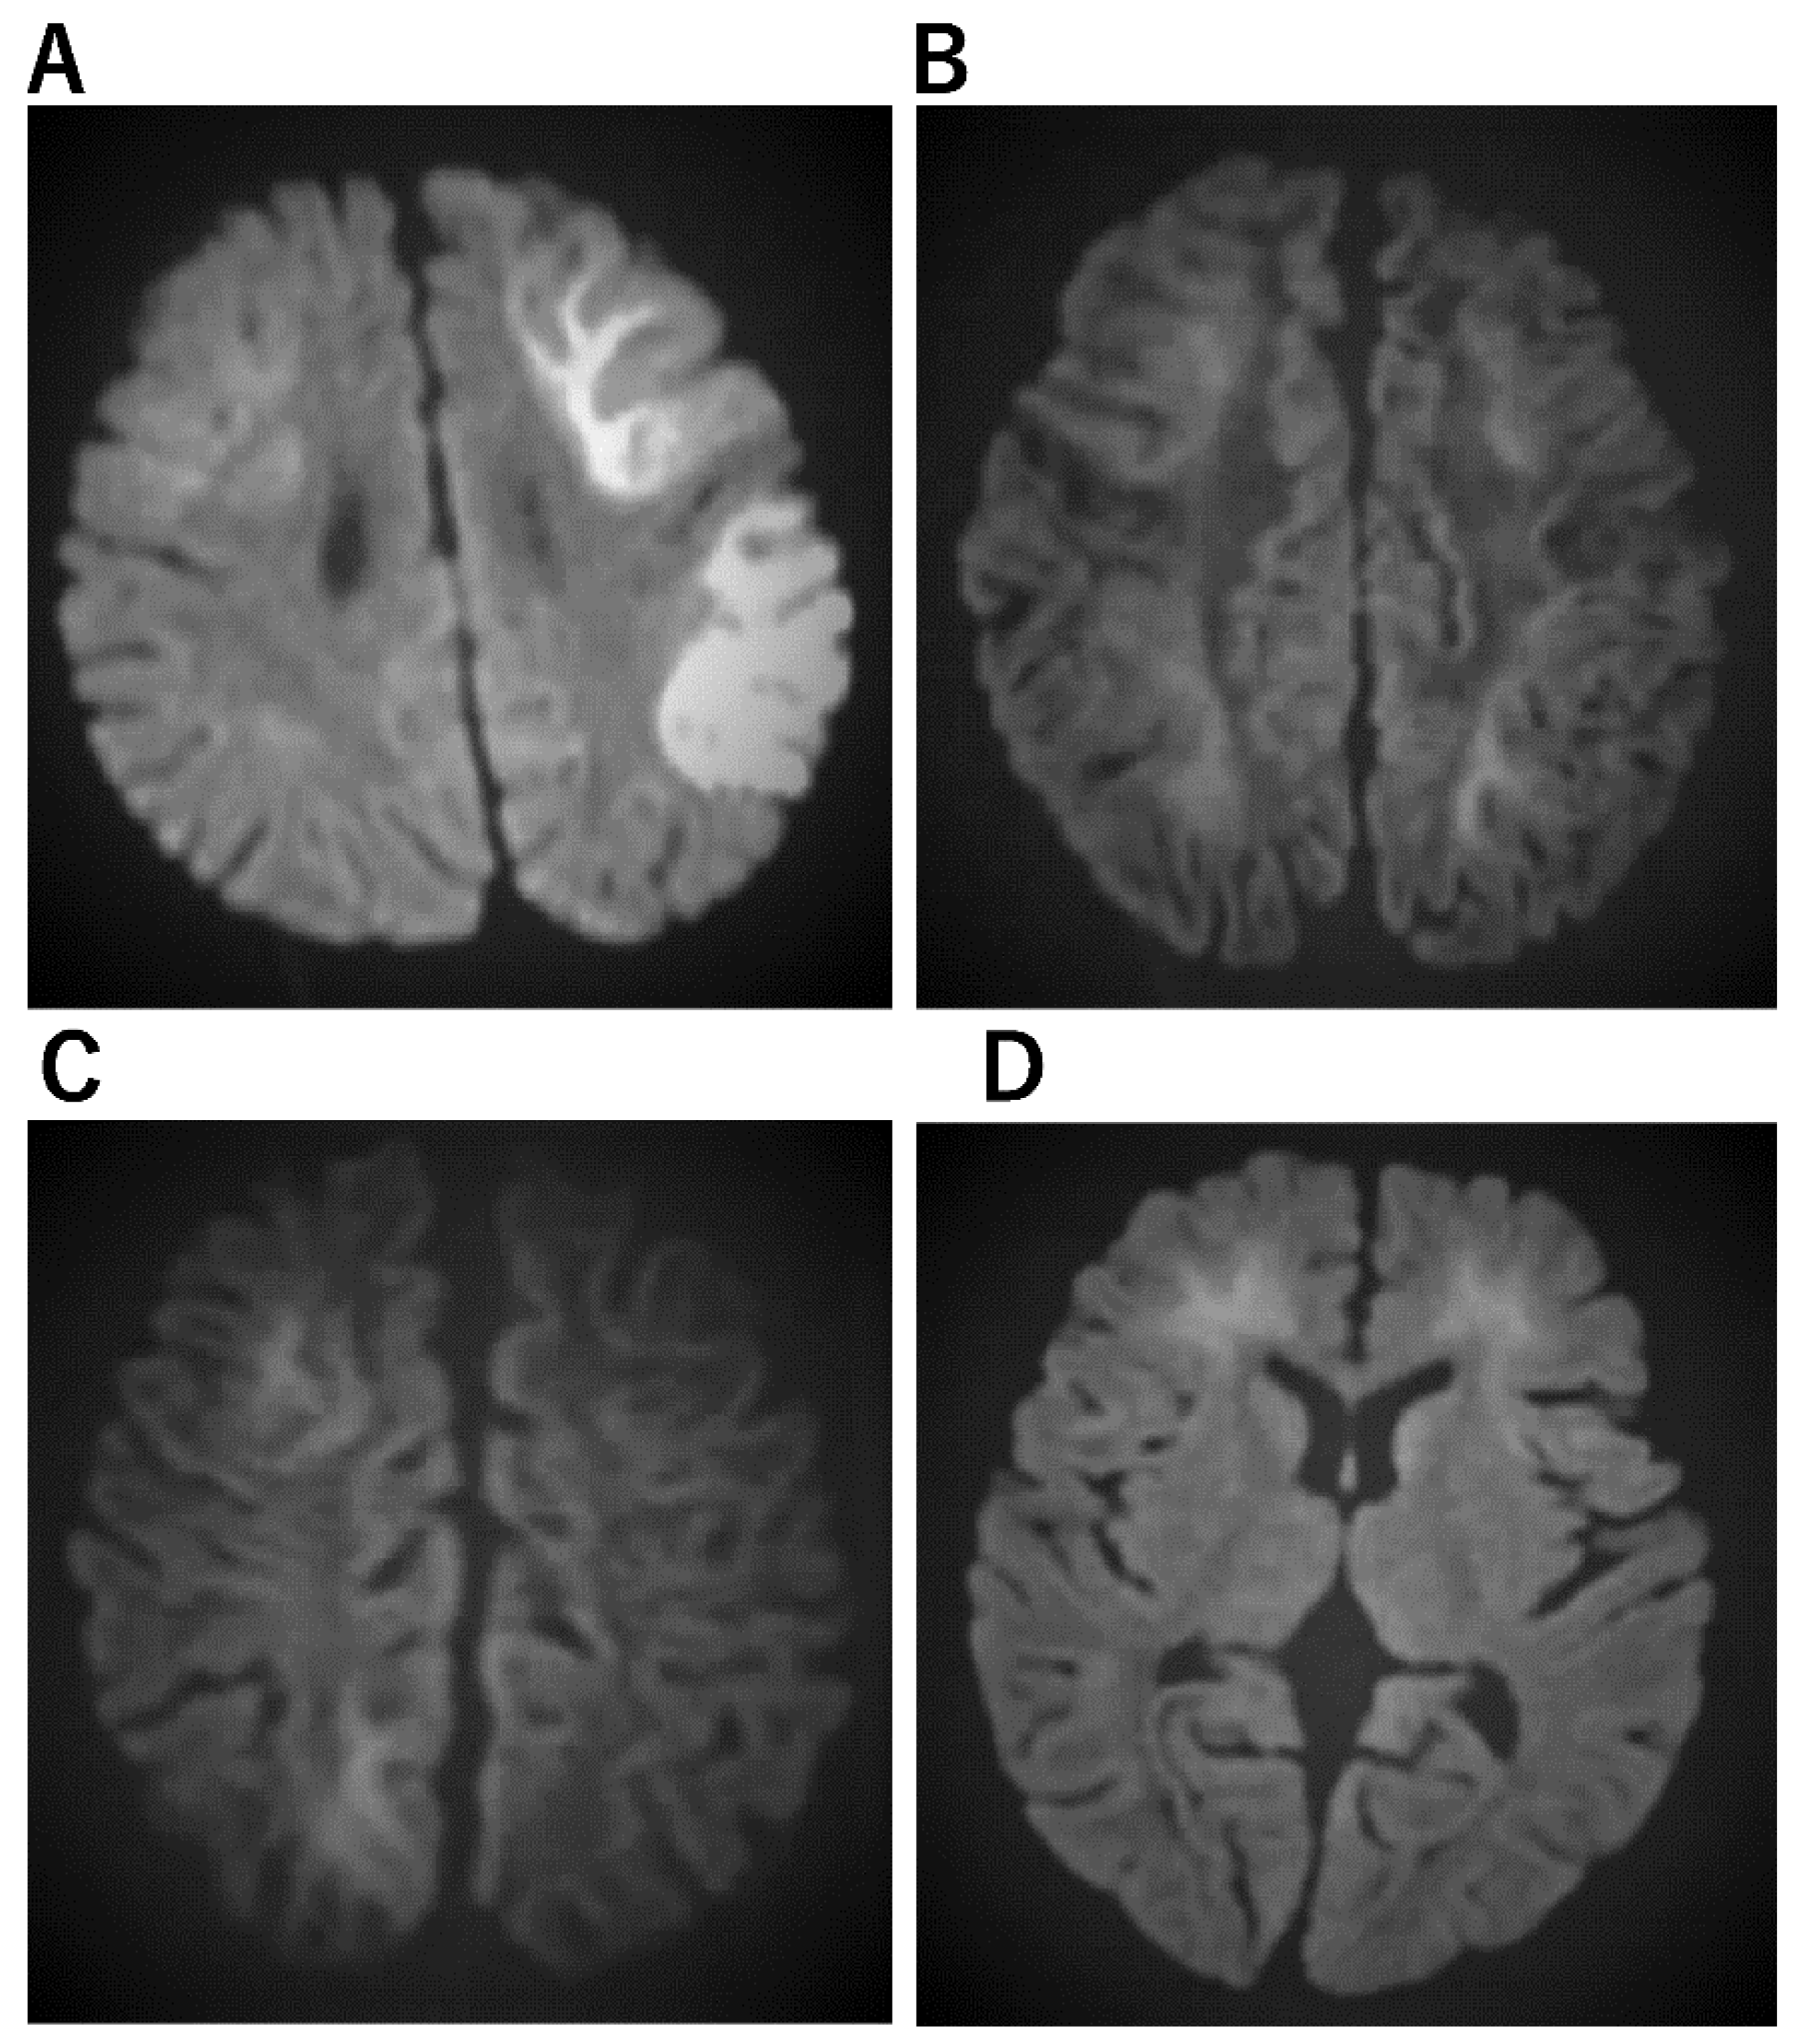

| Acute infantile encephalopathy (AIEF) [51] | a. Postictal edematous changes in the white matter and cortex of both frontal lobes. b. Reduced perfusion in the frontal lobes occasionally persisted and was linked with increasing bilateral atrophic alterations and prolonged high signal intensity on T2-weighted images. |

| Acute encephalopathy with febrile convulsive status epilepticus (AEFCSE) | a. Bright tree appearance of subcortical white matter on MRI/DWI with central sulcus being spared. b. Residual atrophy in the frontal region, or frontal and parietal combined region on CT or MR. |

| AEFCSE | ||||

| Develops with prolonged febrile convulsion, followed by mild unconsciousness, then subsequently provoking a cluster of convulsions (late seizures) with a comatose state. | Incidence is higher in Asian countries, especially Japan | Pyrexia followed by partial seizures and subsequently hemiconvulsions. Transient neurological symptoms and Intellectual disability, attention deficit | EEG findings showed slow waves predominantly on the right hemisphere and a high signal in the subcortical white matter as with the cerebral lobar distribution pattern. Acute infantile encephalopathy predominantly affects the frontal lobes (AIEF). Thermolabile genotype of CPT II variations consisting of three single nucleotide polymorphisms in exons 4 (1055T > G/F352C and 1102G > A/V368I) and 5 (1939A > G/M647V) | TTM |